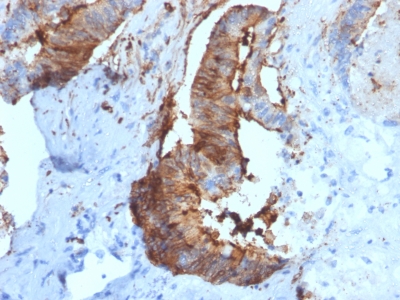

IHC (Immunohistochemistry)

(Formalin-fixed, paraffin-embedded human Renal Cell Carcinoma stained with Cathepsin D Mouse Monoclonal Antibody (CTSD/2781).)